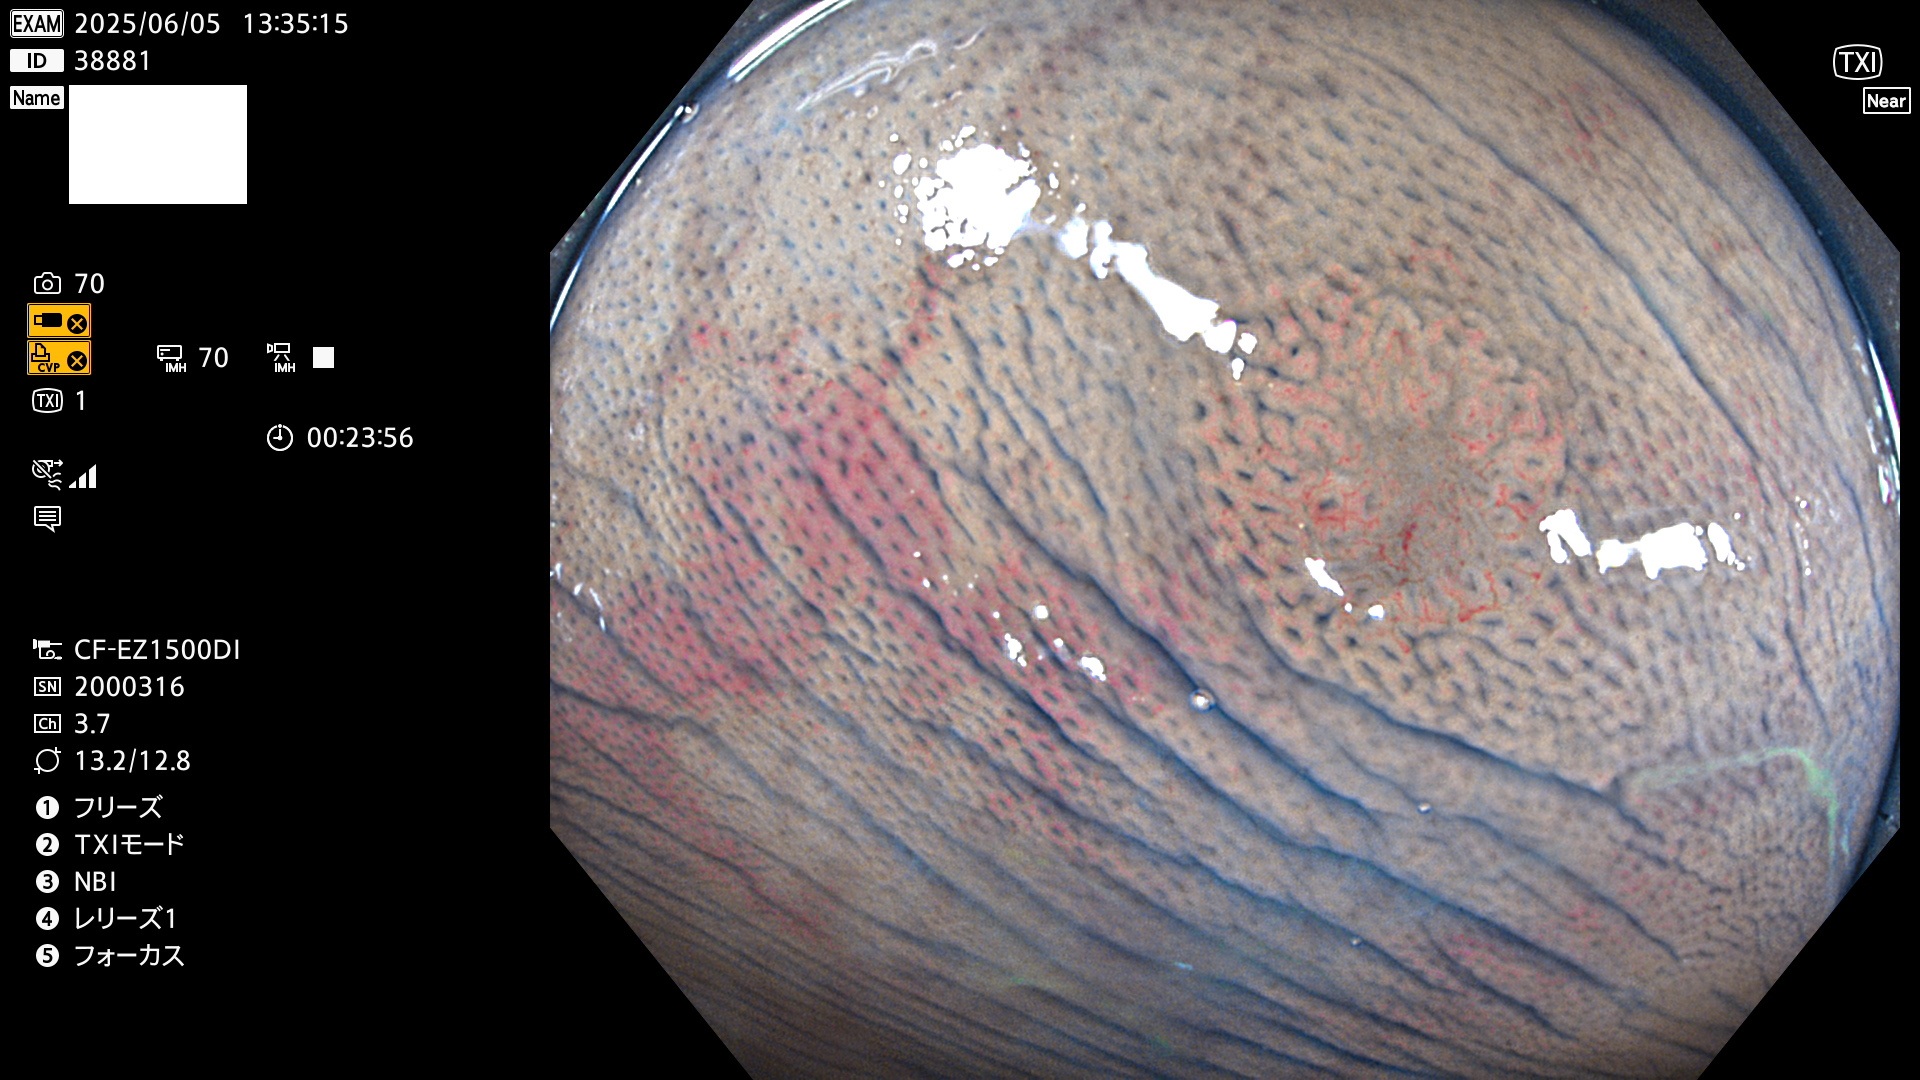

抽出の対象期間 2025年6月5日〜6月8日の4日間(48件の検査)4個 (4/48=8%)